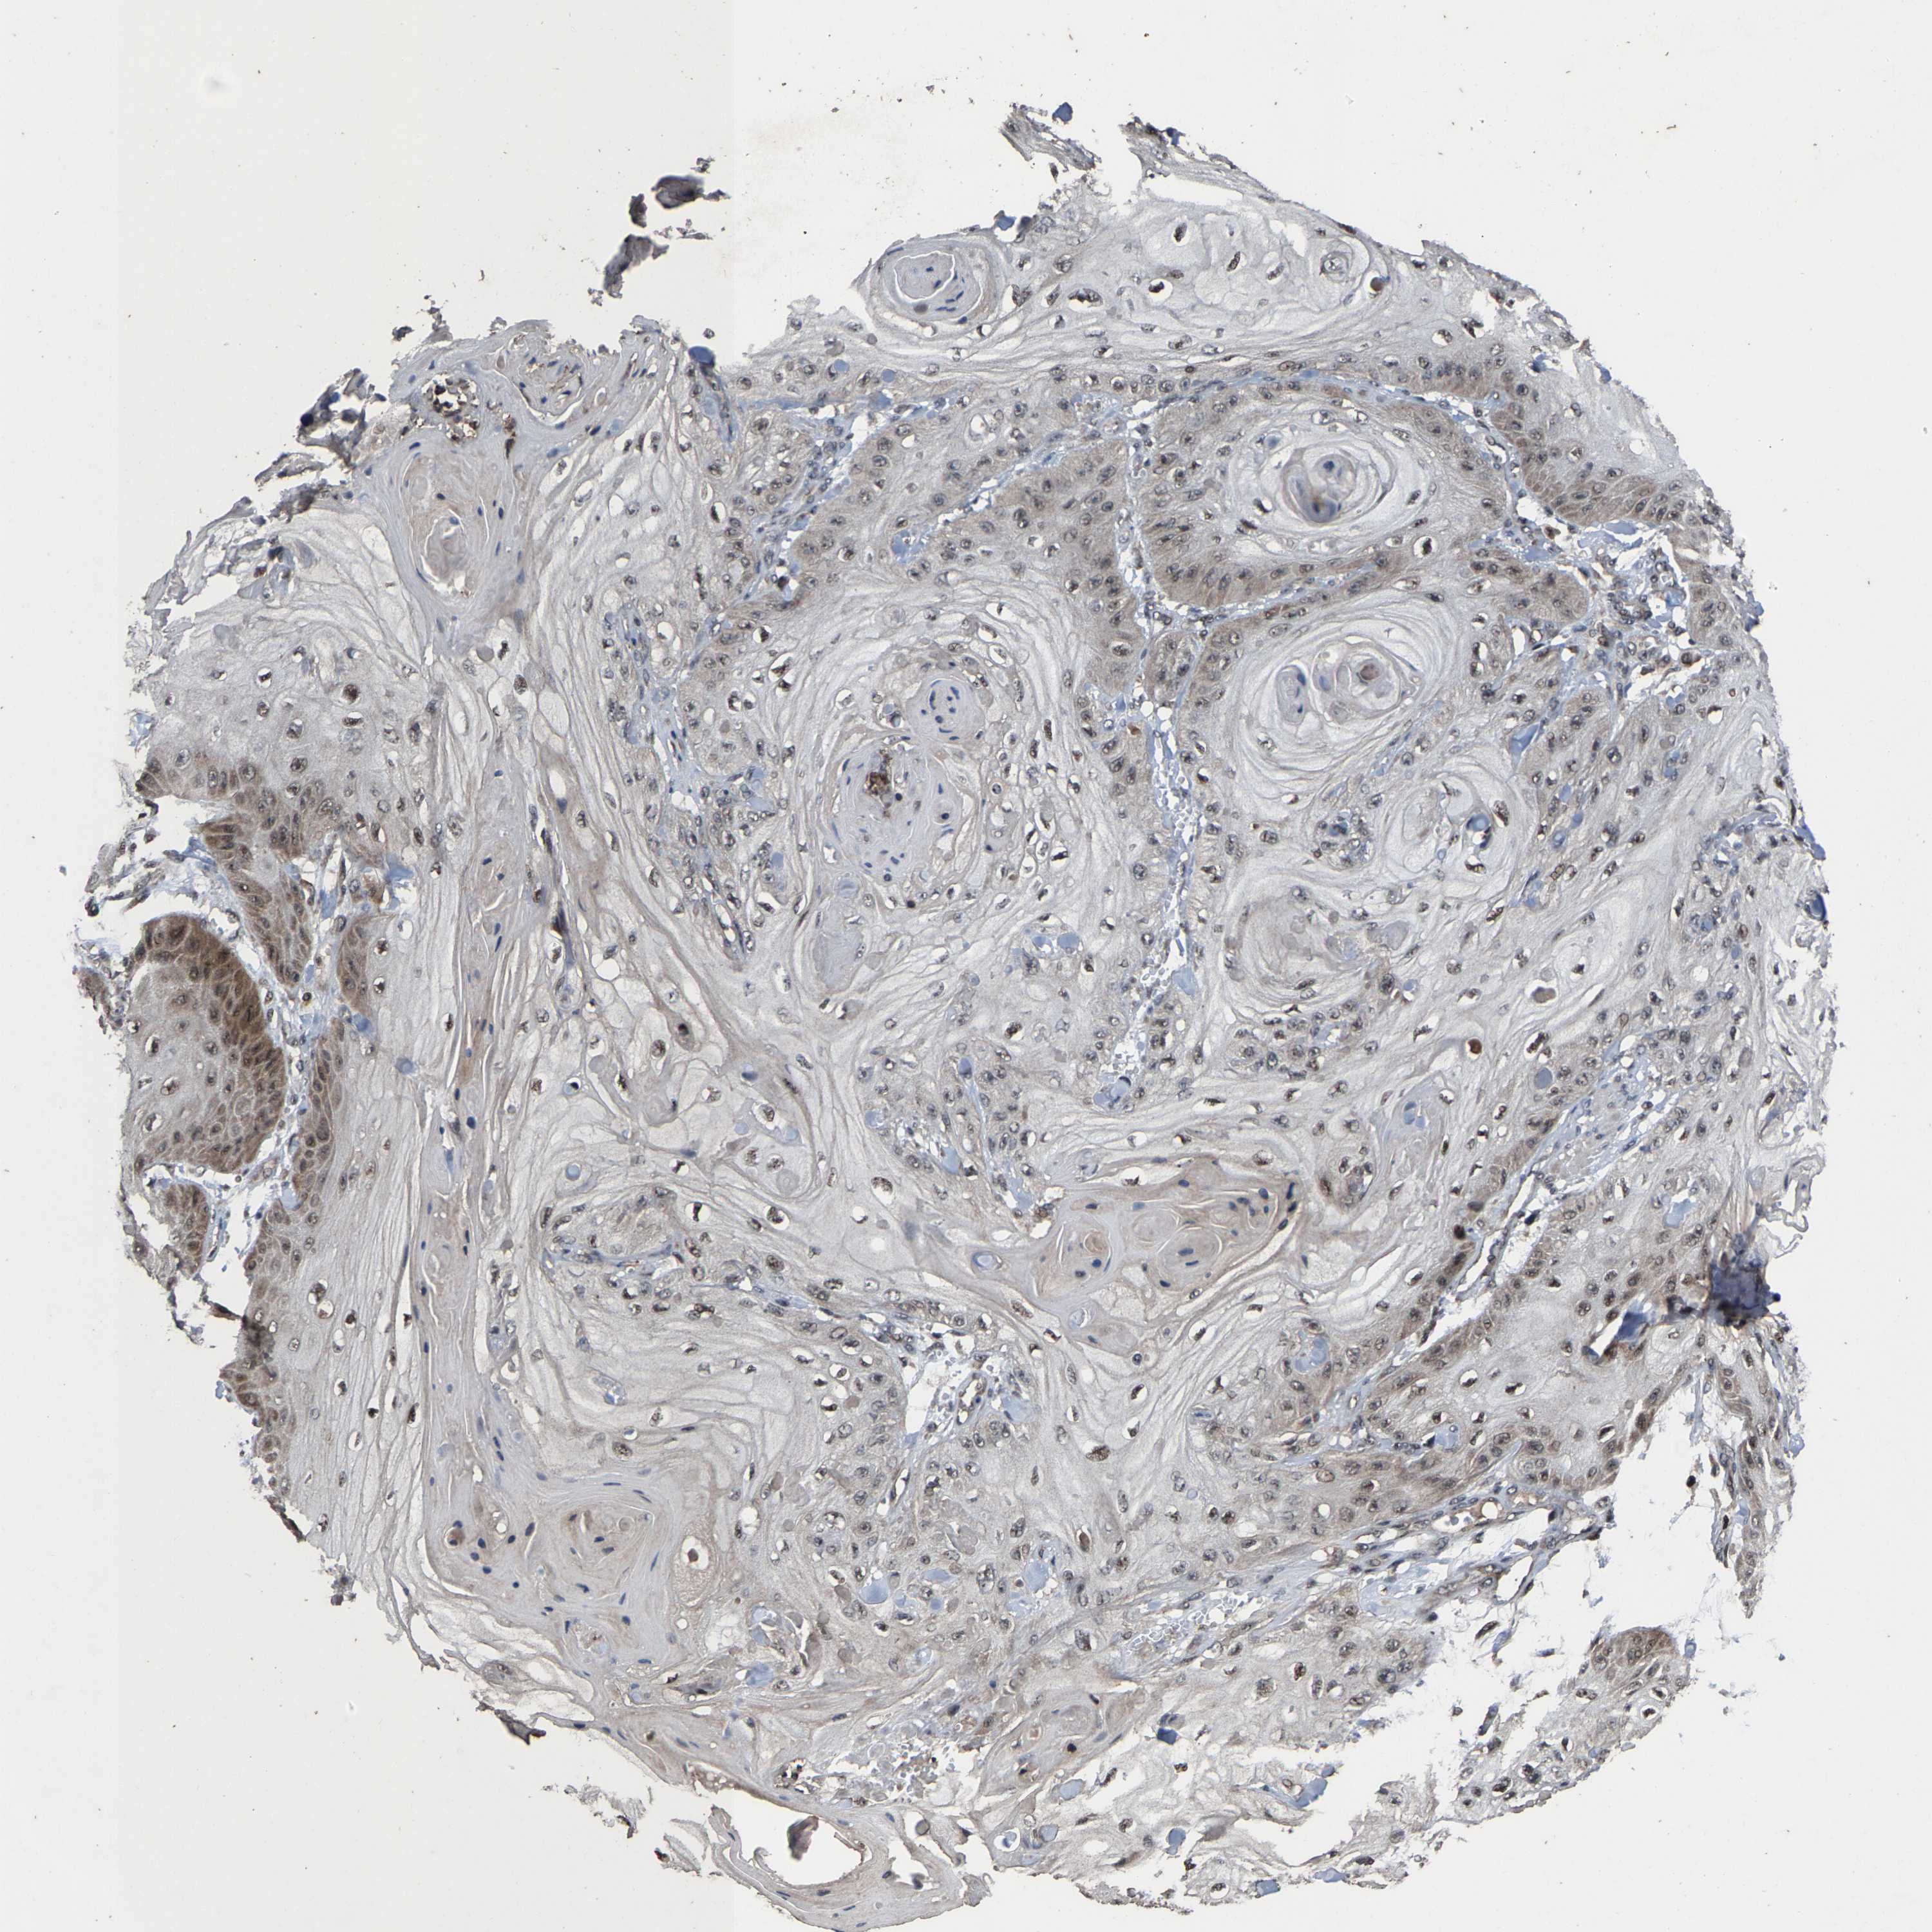

Basal cell and squamous cell cancer

SKIN CANCER - Protein expressioni

A mouse-over function shows sample information and annotation data. Click on an image to view it in a full screen mode. Samples can be filtered based on level of antibody staining by selecting one or several of the following categories: high, medium, low and not detected. The assay and annotation is described here.

Antibody stainingi

Antibody staining in the annotated cell types in the current human tissue is reported as not detected, low, medium, or high, based on conventional immunohistochemistry profiling in selected tissues. This score is based on the combination of the staining intensity and fraction of stained cells.

Each image is clickable and will lead to virtual microscopy that enables deeper exploration of all samples and also displays staining intensity scores, fraction scores and subcellular localization as well as patient and tissue information for each sample.

Antibody HPA020960

Antibody HPA020965

Staining

High

Medium

Low

Not detected

Intensity

Strong

Moderate

Weak

Negative

Quantity

>75%

75%-25%

<25%

None

Location

Nuclear

Cytoplasmic/membranous

Cytoplasmic/membranous,nuclear

Basal cell carcinoma

Squamous cell carcinoma, NOS

Squamous cell carcinoma, metastatic, NOS